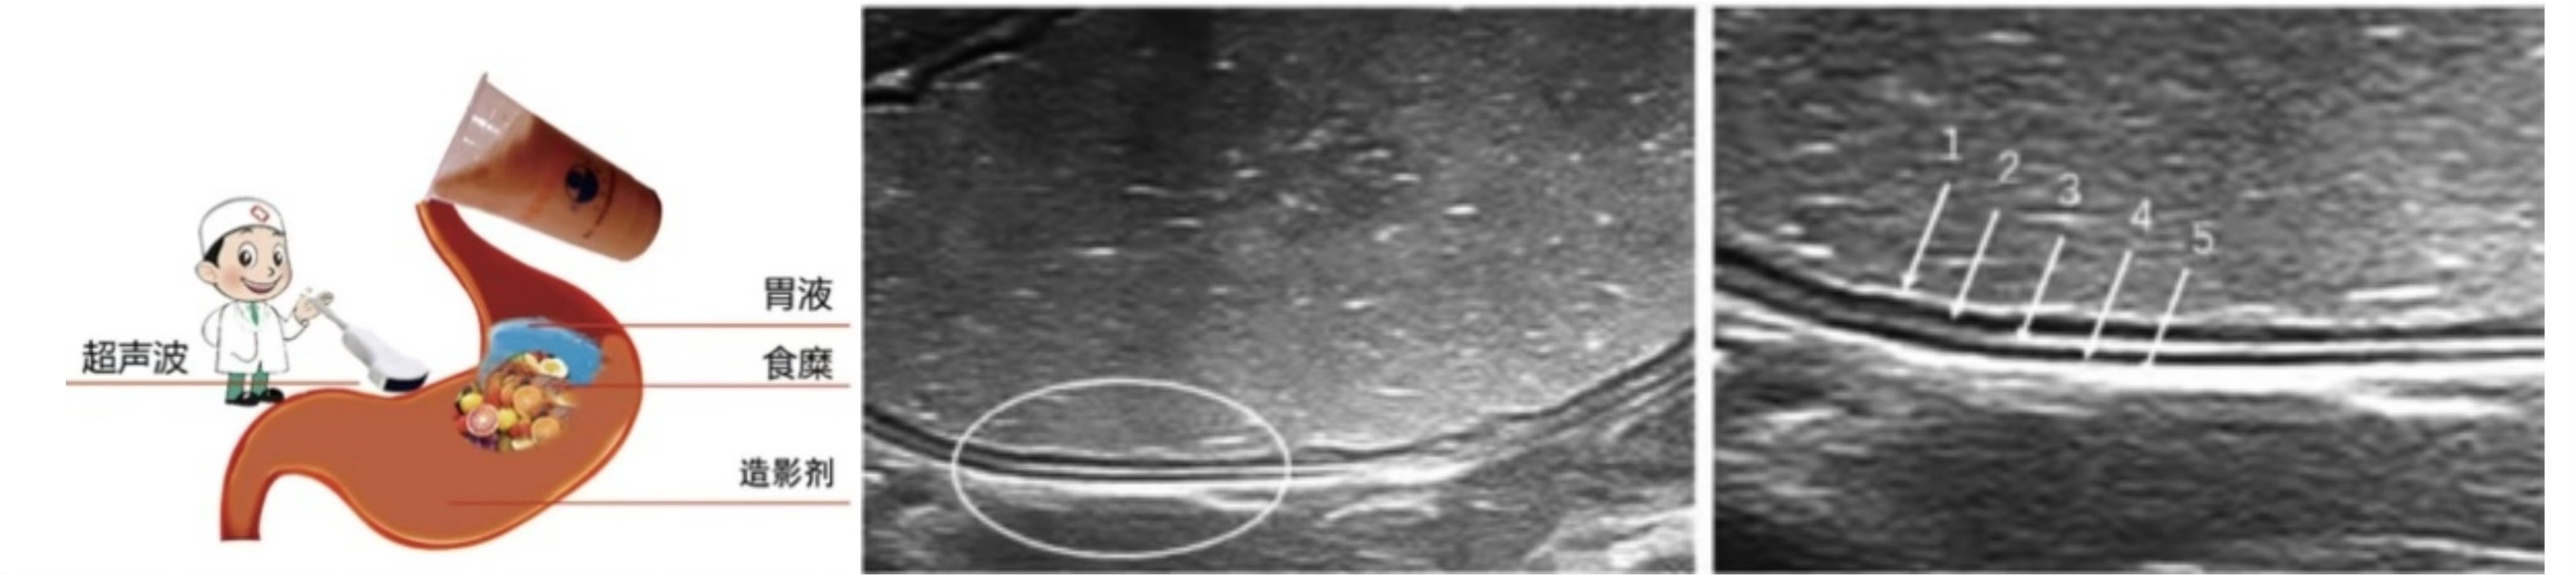

胃充盈超声检查是指患者在检查前口服超声助显剂,也就是一碗香喷喷的“养生粥”,排空胃腔内气体使胃腔充盈,在胃腔形成一种均匀分布的较强回声界面,可清晰地显示胃壁层次结构以及病变,同时为腹腔结构提供了一个声窗,还可以帮助观察以往难以发现的邻近脏器病变。

正常胃壁